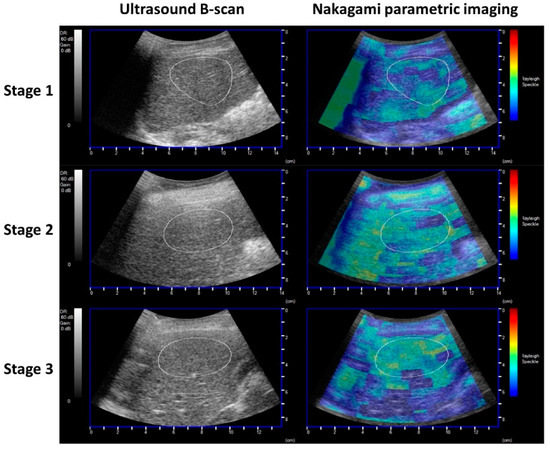

2.3. Ultrasound Examination for Hepatic Steatosis Assessment

- Weng, W.C.; Tsui, P.H.; Lin, C.W.; Lu, C.H.; Lin, C.Y.; Shieh, J.Y.; Lu, F.L.; Ee, T.W.; Wu, K.W.; Lee, W.T. Evaluation of muscular changes by ultrasound Nakagami imaging in Duchenne muscular dystrophy. Sci. Rep. 2017, 7, 4429. [Google Scholar] [CrossRef] [Green Version]